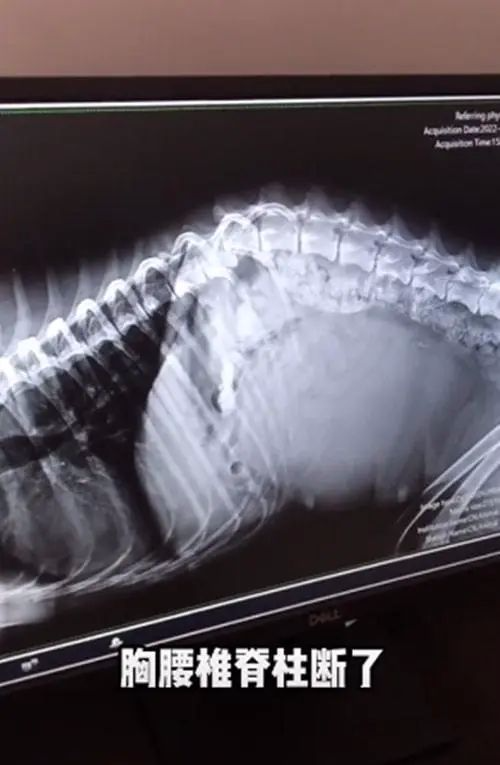

当医生给它拍了片子后,才发现它伤得有多重。

原来流浪狗的胸腰锥脊柱已经断了,导致它的神经受损,现在已经没有办法在自主排尿了,怪不得它浑身都湿透了。